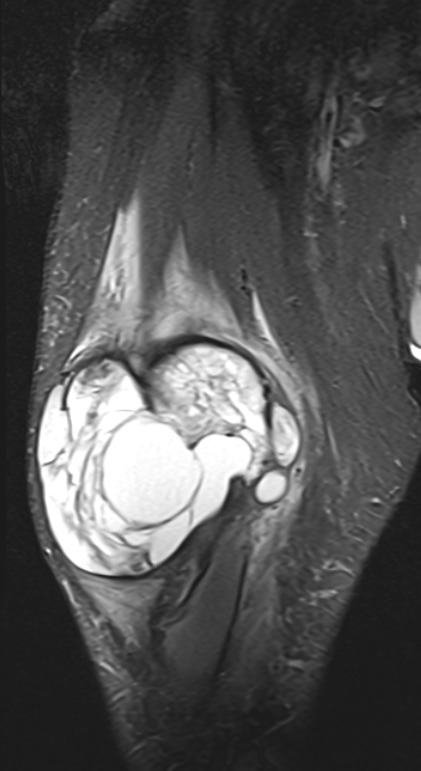

Healthy Eye

Blast Eye